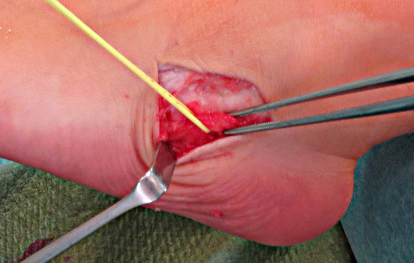

• Hautschnitt: Von der Außenknöchelspitze bis über den Sinus tarsi, ggf. distal etwas nach dorsal auslaufend. (Bild 6,7)

• Darstellen und ggf. Anschlingung des N. suralis. (Bild 8a)

• Inzision des Sinus tarsi unter der Schutz der Peronaealsehnen und der N. suralis. (Bild 8b,9,10)